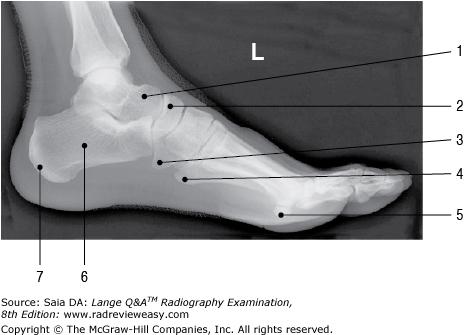

Which projection of the foot will best demonstrate the longitudinal arch?

A Mediolateral

B Lateromedial

C Lateral weight-bearing

D 30-degree medial oblique

-The bones of the foot are arranged to form a number of longitudinal and transverse arches. The longitudinal arch facilitates walking and is evaluated radiographically in lateral weight-bearing (erect) projections. Recumbent laterals would not demonstrate any structural change that occurs when the individual is weight-bearing erect.